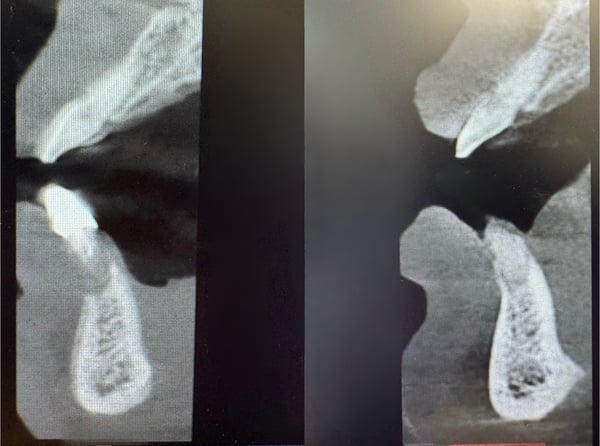

This case involved a 70-year old male who presented with a failing bridge in the lower right posterior quadrant.